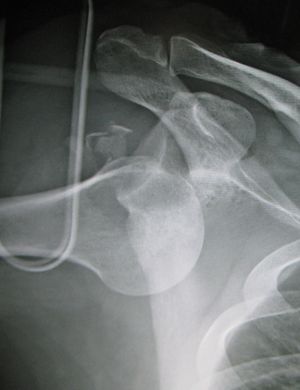

النقطة المضيئة تشير لخلع الكتف الخلفي على الجهة اليسرى. على اليمين، نفس الكتف بعد إجراء عملية الرد.

خلع الكتف الخلفي من الحالات الشائعة، وعادة ما يحدث بسبب انقباض العضلات بسبب صدمة كهربائية أو التشنج.[5] وقد يحدث نتيجة عدم توازن العضلاات المحيطة بالكتف. عادة ما يحمل المريض ذراعه بصورة دائرية إلى الداخل، كما تضعف العضلات المحيطة بالكتف مع حالة إصابة واضحة في النتوء الغرابي.

قد يحدث الخلع الخلفي لأسباب غير معروفة، وخاصة بين كبار السن[11] وفي حالات الصدمة الغير واعية.[12] في دراسة لمجموعة من 40 حالة، لوحظ أن الفترة بين الإصابة والتشخيص تصل إلى عام.[13]